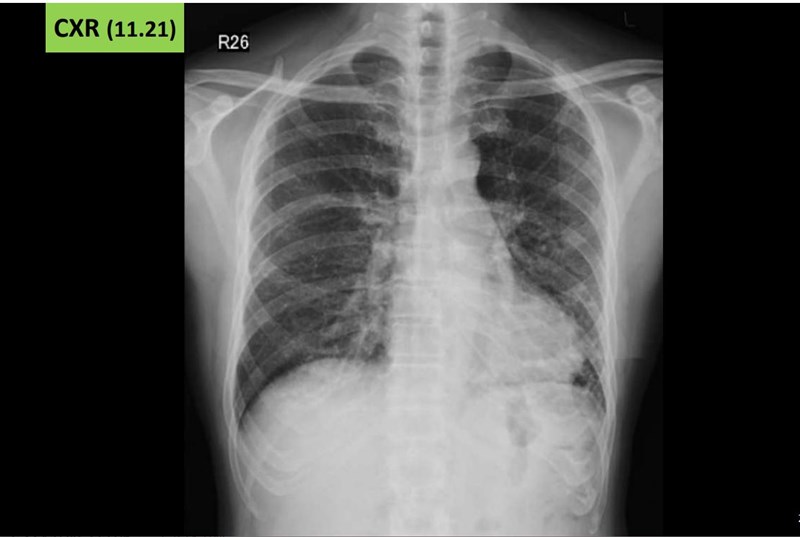

56歲男子嘗試電子菸,短短吸兩周後開始不舒服,兩個月後發現肺部嚴重損傷。圖/王鶴健提供

【本報台北訊】使用電子煙短短兩周竟引發嚴重肺損傷。一名56歲男子一天一包菸,連續抽38年,有天老菸槍想嘗試電子菸,短短吸兩周後發現,運動開始會喘、乾咳,甚至食慾開始變差。他的症狀持續兩個月後,決心要戒菸,赴門診檢查發現,肺部已經泛白浸潤,有發炎現象,肺功能降到同齡者的6、7成,確診肺損傷。

該男子經檢查發現,肺部確實有異常,肺功能降到同年齡層的6、7成,肺容量已明顯變小,氣體交換變差,甚至住院沒有改善,進一步切片發現,肺部有纖維化現象。王鶴健提醒,電子菸成分不明,有些不良業者甚至會加入大麻油成分,這都是加速急性肺損傷的因素。